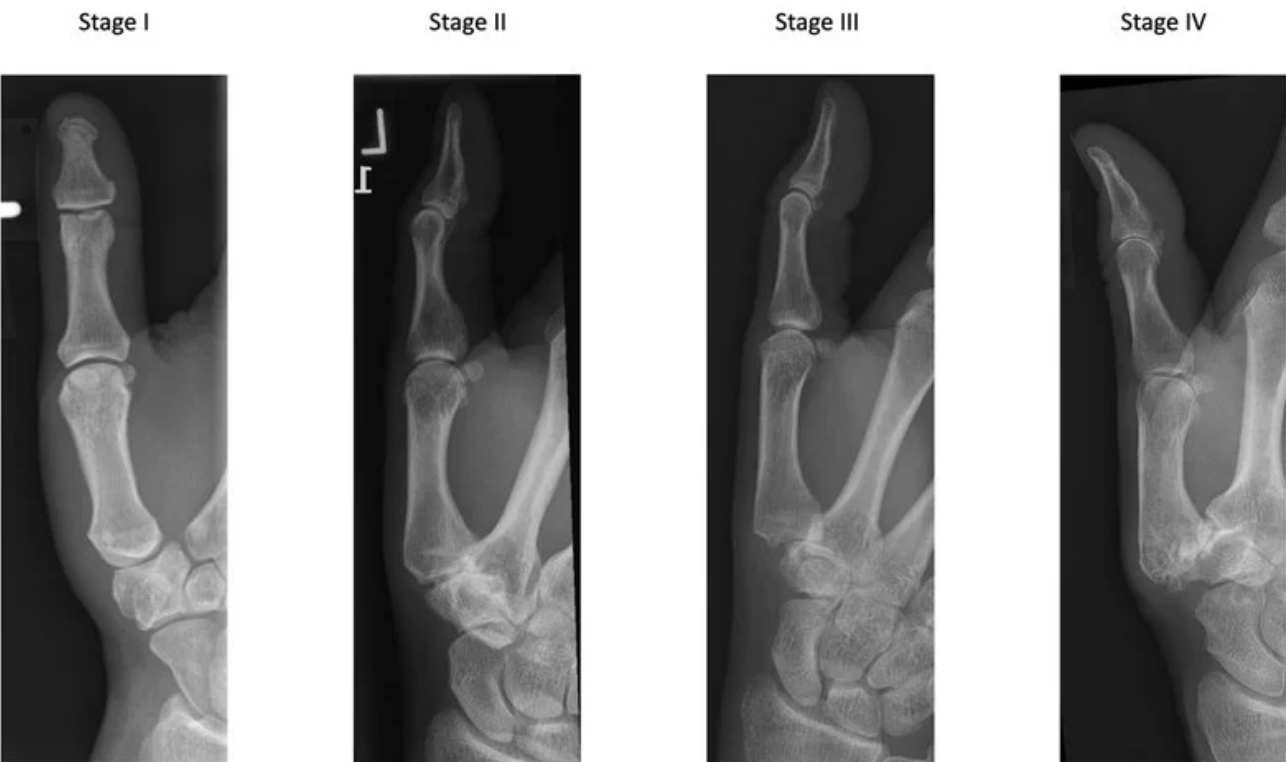

A classificação mais utilizada é a de Eaton e Littler, baseada nos achados radiográficos. Ela descreve a evolução da doença desde fases iniciais, com discreta alteração articular, até estágios avançados com destruição da articulação e comprometimento de estruturas vizinhas .

Um ponto importante é que nem sempre a radiografia corresponde à intensidade dos sintomas. É comum encontrar pacientes com pouca dor e alterações avançadas, assim como o contrário.